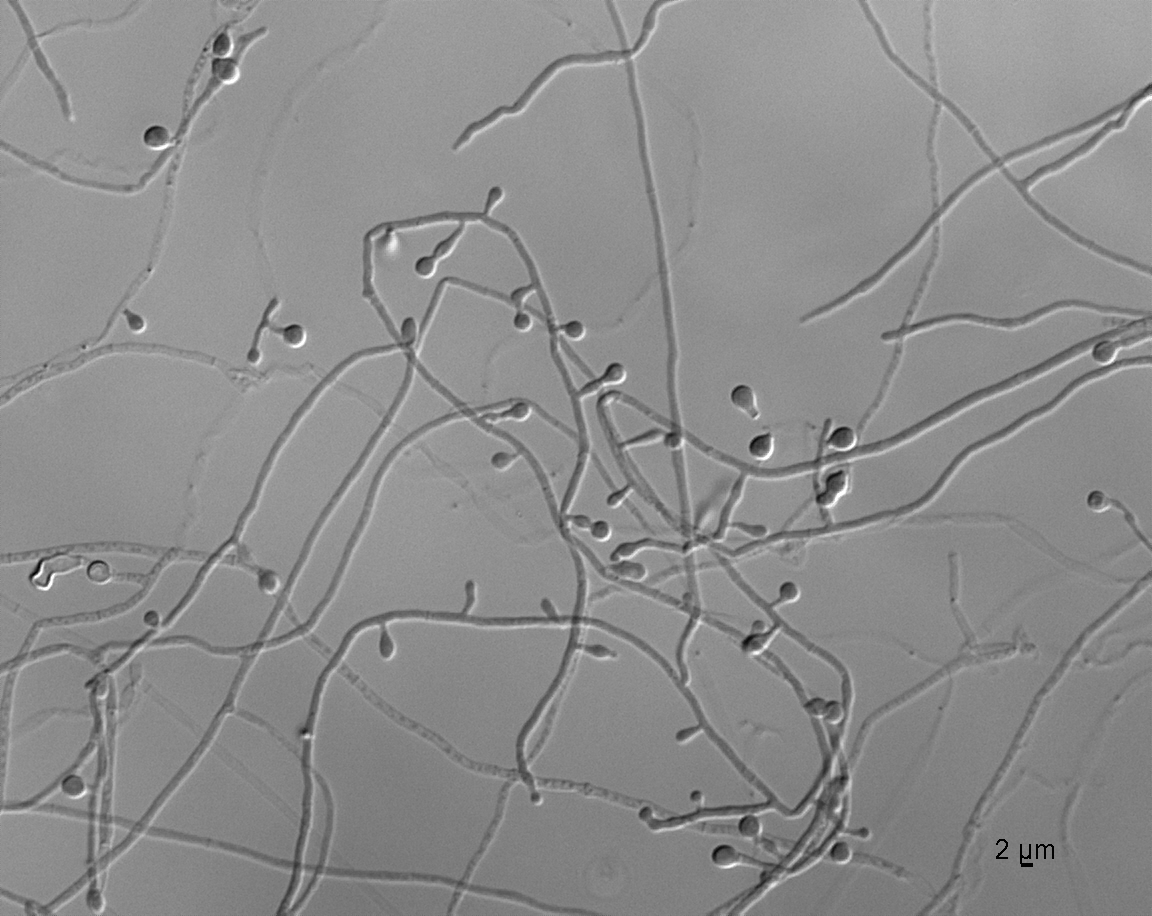

| Species Name: | Blastomyces dermatitidis |

| Taxonomy: | FUNGI Ascomycota, Eurotiomycetes, Onygenales, Ajellomycetaceae |

| Substrate: | lung biopsy, male 43 yr, with nodule in lung; DE-calcofluor + for fungal elements | Location: | CANADA Saskatchewan, Regina, Regina Qu'Appelle Health Region (GEO: 50.445,-104.619) |

| Characters: | HUMAN/ ANIMAL PATHOGEN Blasto probe + - (Click for publications citing UAMH 10592) |